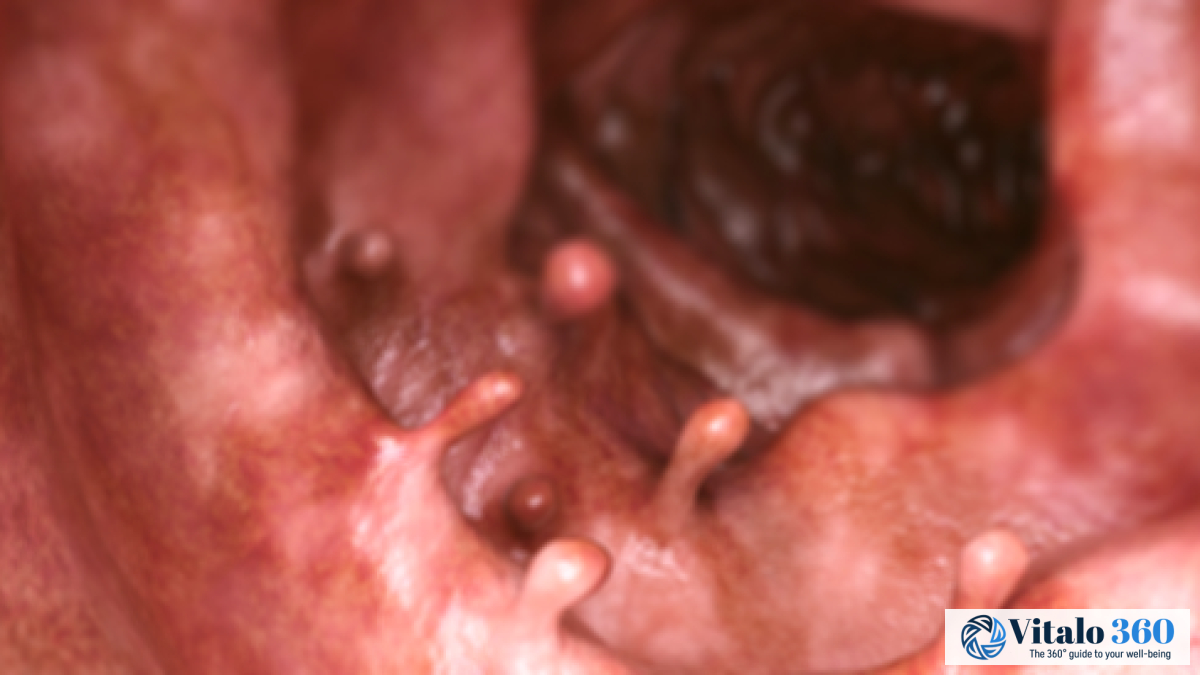

- Endoscopy: This is where they stick a tube with a camera up there.

- Colonoscopy: Super common way to check things out, it helps to see what’s really going on.

After chemo, radiation therapy is sometimes used, where they’ll zap the cancerous tissues. They use beams of lasers, while checking everything with endoscopy.